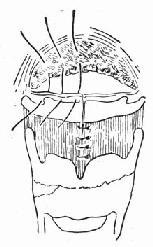

(1)急性声门上损伤:声门上损伤包括甲状软骨板上半部骨折和会厌损伤(图96-1)。有急性喉阻塞者首先行常规气管切开术,然后行前连合直接喉镜检查,注意喉水肿和喉及下咽粘膜裂伤的情况。手术包括缝合粘膜裂口并切除会厌及会厌谿之血肿组织,颈前在舌骨水平做横切口,剪断舌骨后,给行切开甲舌膜进入咽腔(图96-2)。切除会厌,会厌根部血肿组织及双侧假声带(图96-3)。用丝线缝合喉粘膜,尽量对合复位骨折的甲状软骨板,并用丝线缝合甲状软骨外板软骨膜,再缝合甲舌膜(图96-4)。逐层缝合切口。术后48h经鼻咽置入下咽部一条吸引引流管,持续引流。待喉部手术后反应消退,可试行堵管,呼吸道通畅即可拔除气管套管。

图96-4 缝合软骨外板软骨膜及甲舌膜